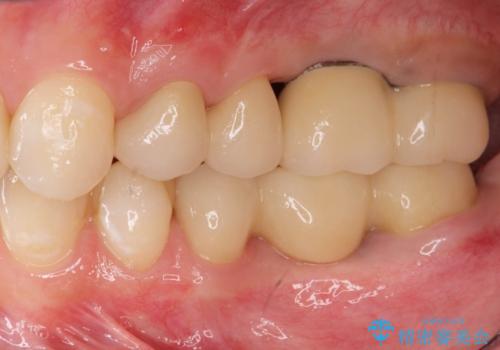

インプラント・セラミック・矯正治療を含む包括歯科診療

- 「地元の歯医者にずっと通っているが、どんどん歯が悪くなる。時間とお金がかかってもいいので徹底的に歯を治したい。」

、と総合的な歯科治療を希望されて来院されました。

虫歯や咬合関係・歯槽骨の吸収・根尖病変・歯の欠損・複合的な問題を一つずつ解決し、

安定した噛み合わせの構築・歯ブラシのしやすい環境の整備・歯内歯周の感染除去・造骨を伴うインプラント治療

を行い、長期的な予後を見込める口腔内環境を確立、整備して行きます。